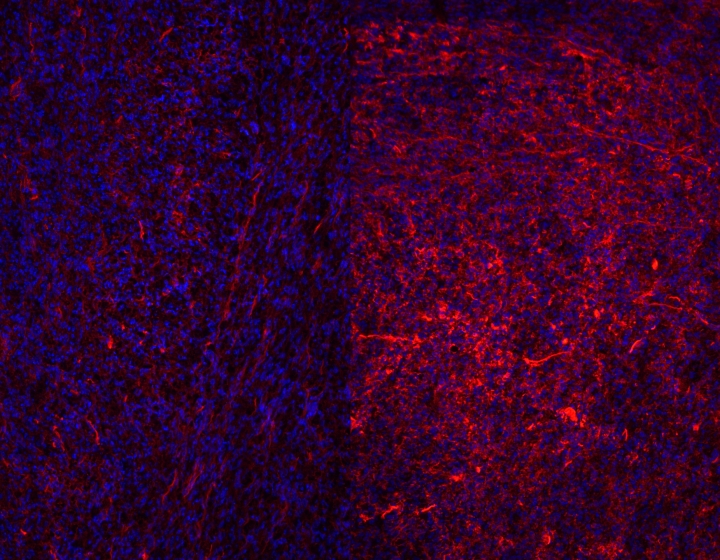

Finally, the Veterinary School has set up a major veterinary diagnostic laboratory, catering to the specific needs of local and regional practitioners.